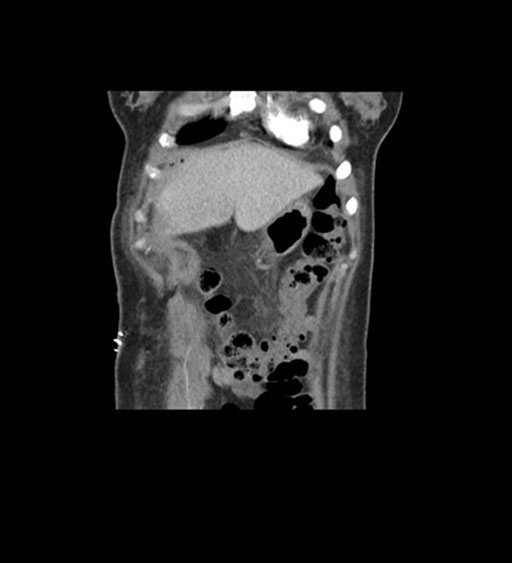

Coronal Arterial